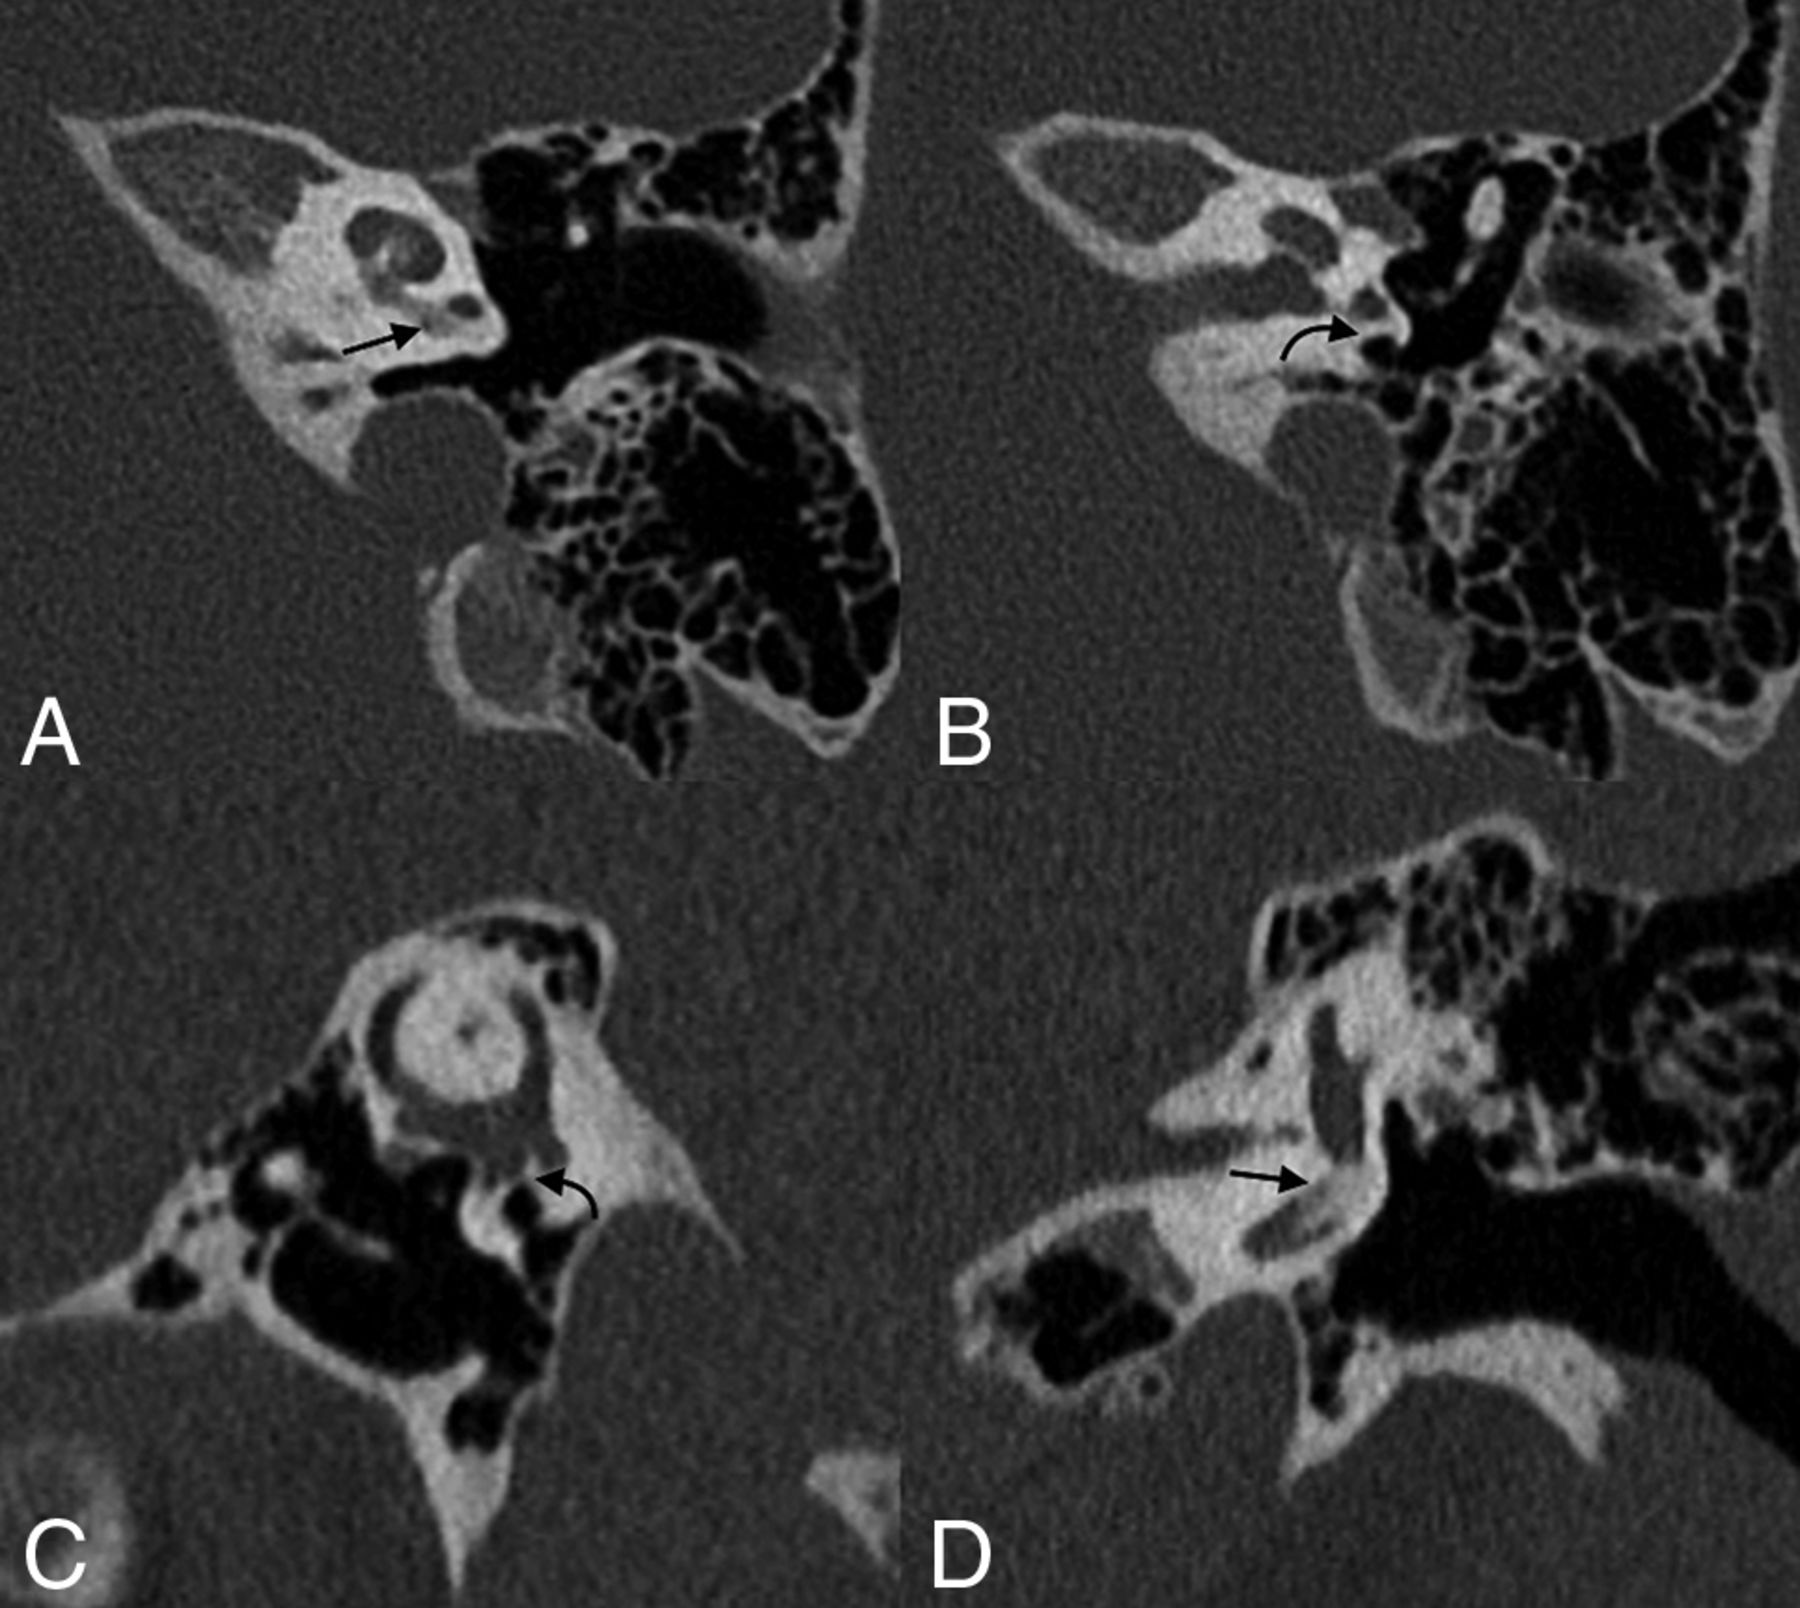

Round window absence is a rare abnormality that may be seen in conjunction with various syndromes, including incomplete partition anomalies, mandibulofacial dysostosis, and Coloboma of the eye, Heart defects, Atresia of the choanae, Retardation of growth and/or development, Genital and/or urinary abnormalities, and Ear abnormalities and deafness (CHARGE) syndrome, in addition to cases of aural atresia (Fig 3).9⇓-11 In very rare cases, it may also occur without an associated syndrome (Fig 4).12,13 Some authors have posited that such nonsyndromic cases may represent an inherited autosomal dominant genetic disorder with variable penetrance.10 Even in nonsyndromic cases, few reports exist of round window atresia as an isolated finding; most of these patients have associated middle ear or pinna abnormalities.10

A 5-year-old girl with round window atresia in the setting of CHARGE syndrome. Axial (A–C) and coronal (D) images of the right temporal bone demonstrate complete absence of the round window (long black arrow, A); the round window niche is hypoplastic and surrounded by bone (dashed arrow, A), adjacent to a preserved sinus tympani (curved white arrow, A). Multiple other anomalies are the following: The stapes is dysmorphic with absence of the neck, crura, and footplate (short white arrow, B); the oval window is absent (long white arrow, B and D); the facial nerve canal is diminutive (short black arrow, C) and inferiorly displaced (short black arrow, D); and the hypotympanum is enlarged (curved black arrow, D). The semicircular canals are absent.

Nonsyndromic round window atresia. Axial (A), coronal (B), and Pöschl (C) views of the right temporal bone of a 10-year-old girl demonstrate an ossification at the expected location of the round window membrane (arrows). The patient had no known syndromic association.

Stenosis of the round window membrane and/or recess is more common than complete round window absence. Like round window atresia, stenosis of the round window can have syndromic associations and contribute to hearing loss.15 The lower limit of normal size for the round window niche is generally cited as being 1.5 mm.1 Nevertheless, imaging characteristics of stenotic recesses can be quite variable, ranging from mild to severe (Fig 5).

Round window stenosis. A 52-year-old woman with profound bilateral hearing loss. Axial (A), coronal (B), and Pöschl (C) images of the right temporal bone demonstrate advanced stenosis of the round window (arrows).